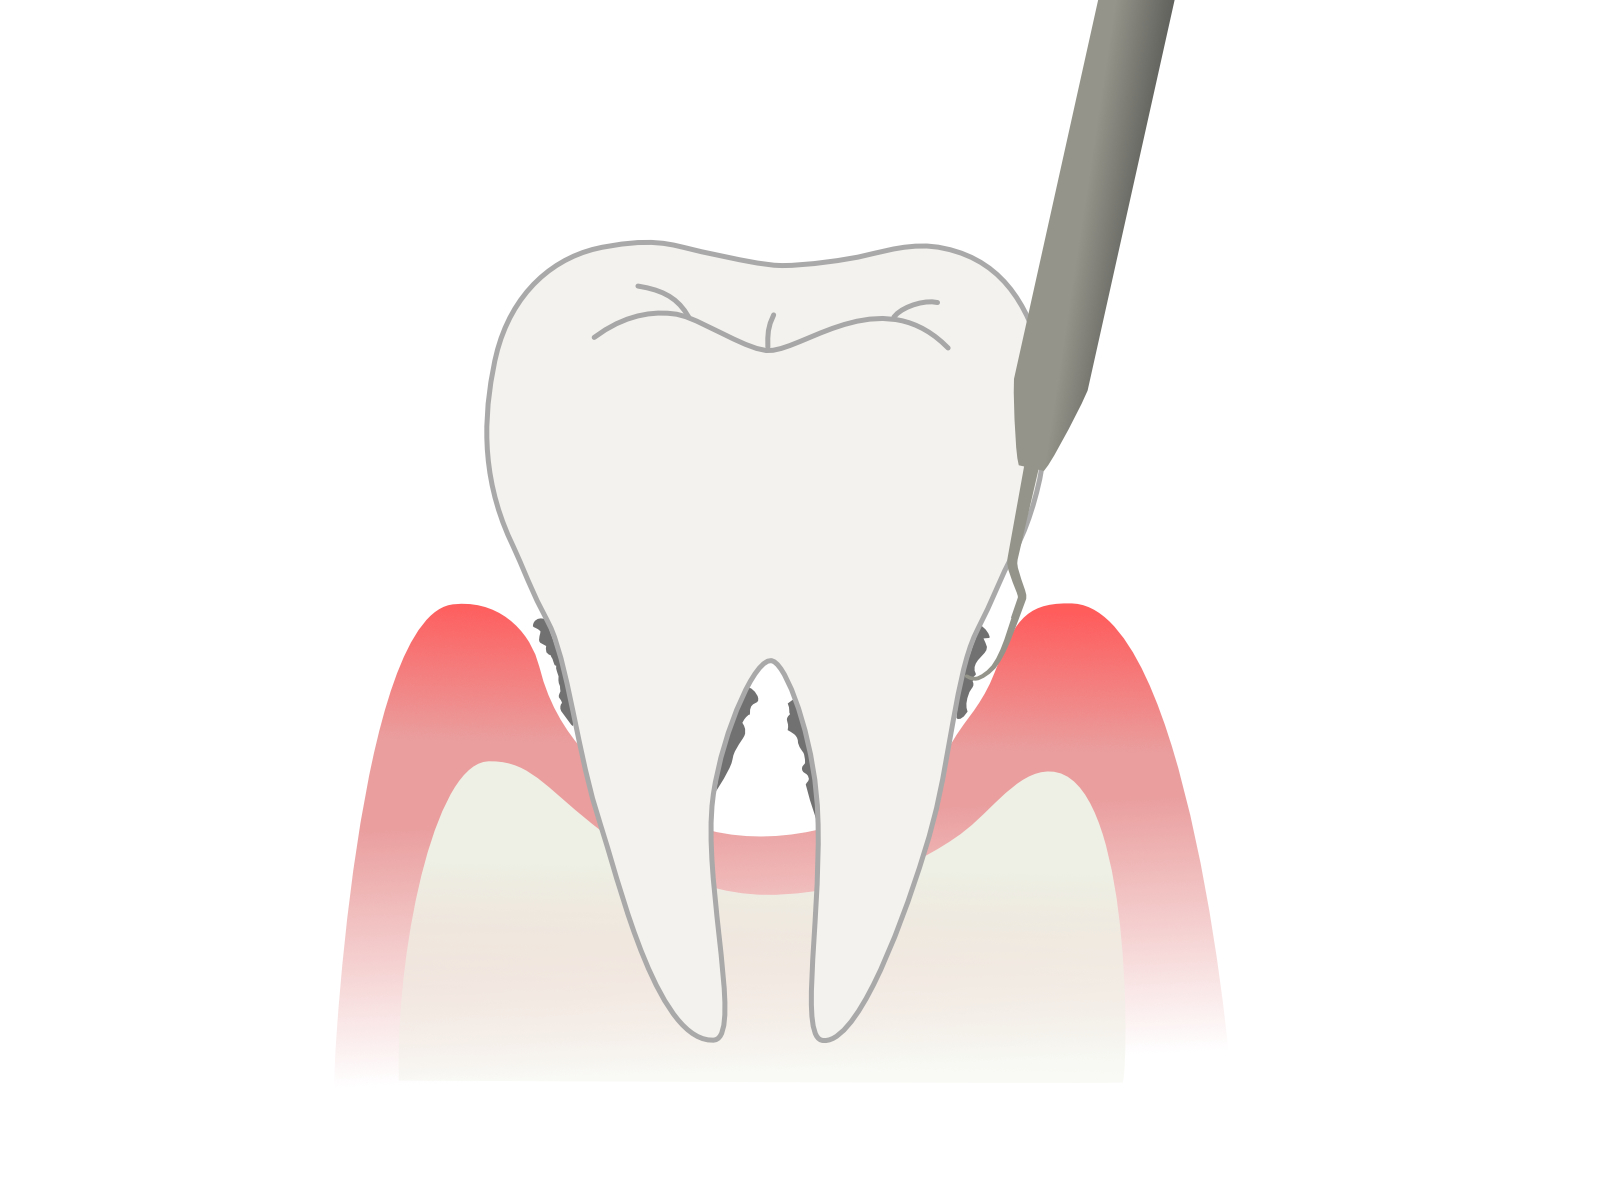

治療部位を20倍以上に拡大できる歯科用顕微鏡マイクロスコープを使用し、肉眼では確認できない歯周ポケット内をしっかりと”見ながら”治療を行います。

どちらのほうが精度の高い治療ができるかは一目瞭然です。

Er:YAGレーザーは、歯周ポケット内の細菌除去、炎症組織の蒸散、歯石の除去補助などに用いられるレーザーで、治療部位の周辺組織への侵襲が極めて低いことや、殺菌効果、治癒を促進する効果があるため、患者さんの負担を減らしながら効率的に歯周病治療ができるのが特徴です。